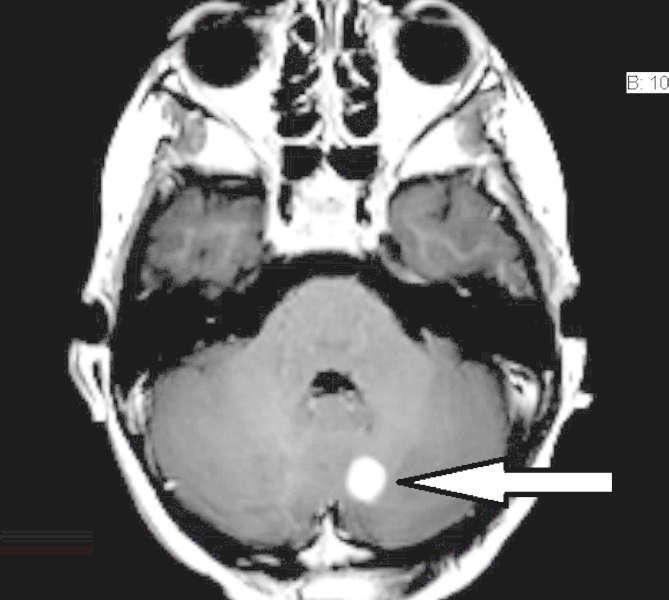

Cerebellar Pilocytic Astrocytoma

The patient has known neurofibromatosis, type I. There are numerous patchy foci of high signal within the cerebellum and the brainstem, and subtle change in the thalami.

There is a very well defined, almost spherical lesion in the medial left cerebellar hemisphere; it is frankly hyperintense on T2 and FLAIR, measuring 13.8 mm AP by 11.0 mm transverse.

On contrast images in three planes, this same lesion measures 10.8 mm AP by 10.8 mm transverse by up to 9.2 mm craniocaudad, which represents an increase in size compared to the previous MRI of 07/16/2014, when it had measured 6 mm.